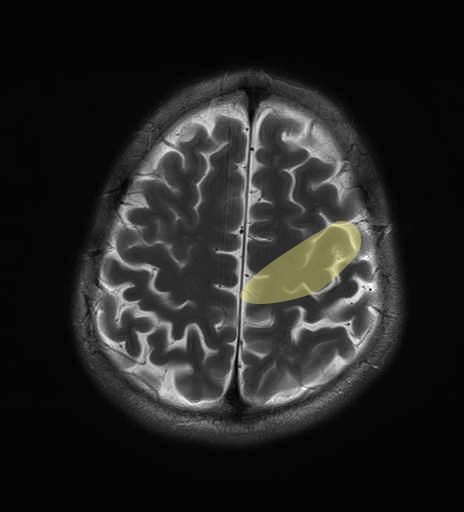

運動系 錐体路系に色を付けました。

■皮質脊髄路(いわゆる錐体路):一次運動野から脊髄遠隔の下位運動ニューロン細胞体まで